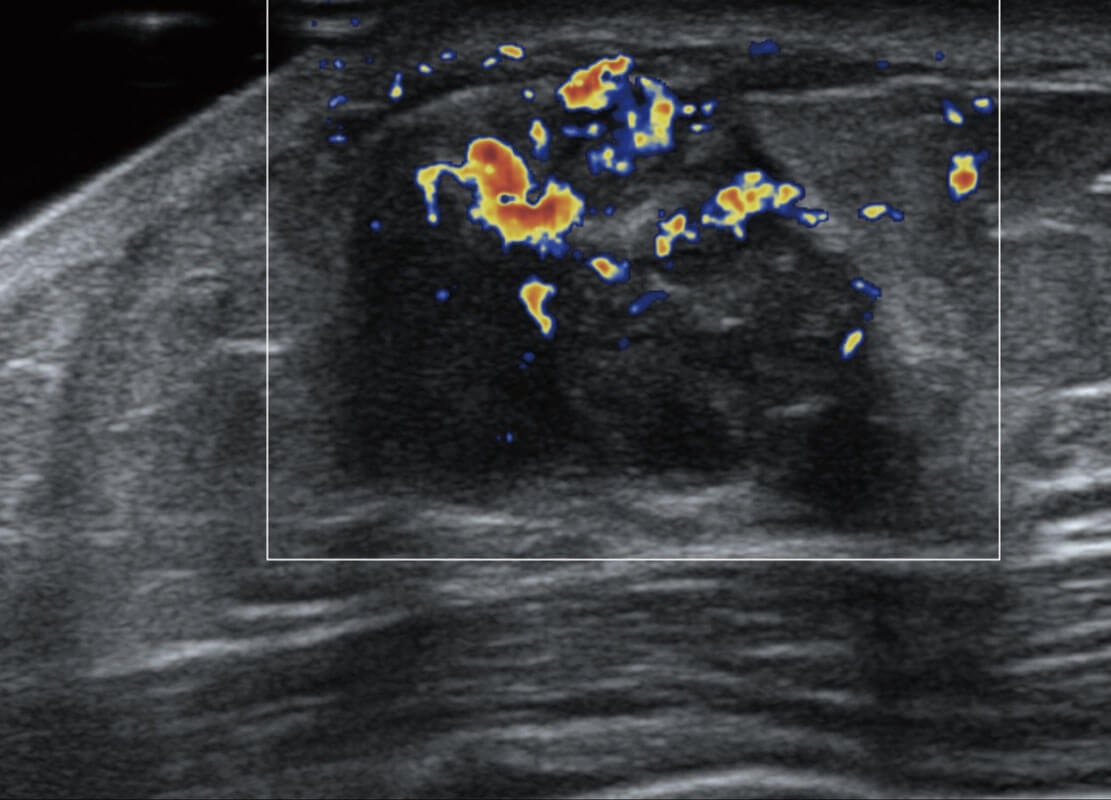

• 乳腺导管癌

• 乳腺癌显微血流